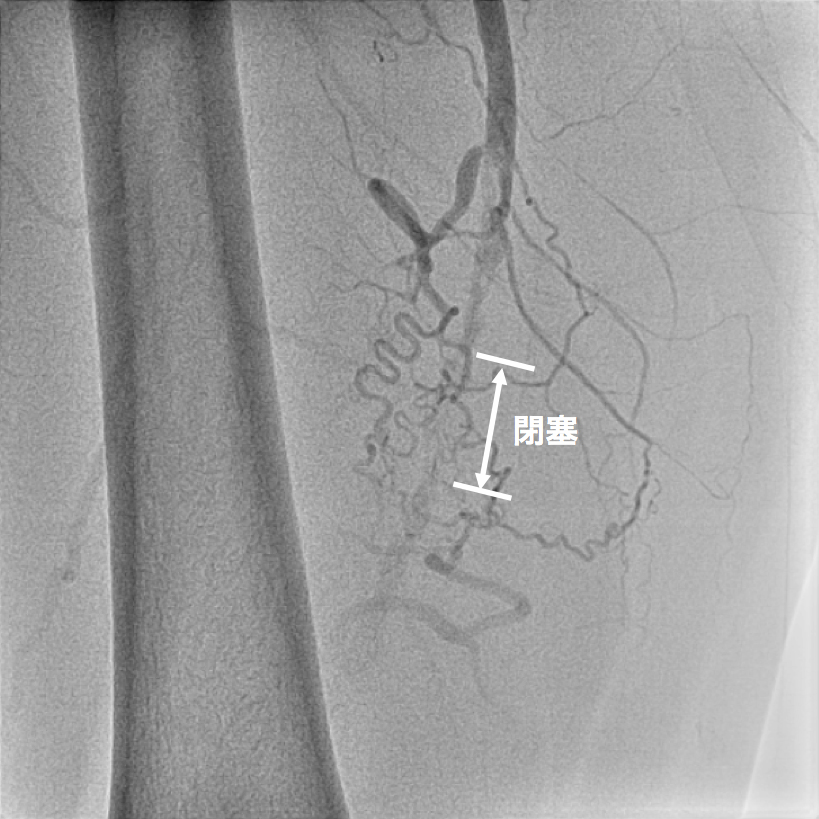

【図5】下肢造影カテーテル検査 カテーテルによる血管造影検査ですが、CT検査 同様に閉塞していることがわかります。